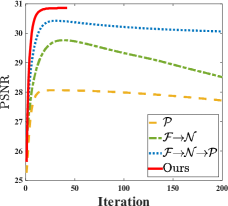

As shows in Fig. 1, at the first several iterations, the loss of is slightly larger than that of . Because the input is corrupted with severe artifacts, thus the role of data-driven module is significant at the first several steps. But as process goes on, repeated denoising operation in turn causes over-smoothing. While module can make up for it by incorporating model based knowledge. Though can improve the performance, it cannot ideally converge to a desired solution. The solid line indicates the superiority of Ours over other choices in both convergence rate and reconstruction accuracy. The execution time of , , and Ours is 4.4762s, 3.3240s, 6.2760s and 2.5225s, respectively. As expect, the proposed method provides a much faster reconstruction process. Thus we can verify that our framework has higher efficiency both in terms of theoretical convergence and practical execution time. The visualized results in Fig. 2 also verify that Ours has better performance than others.